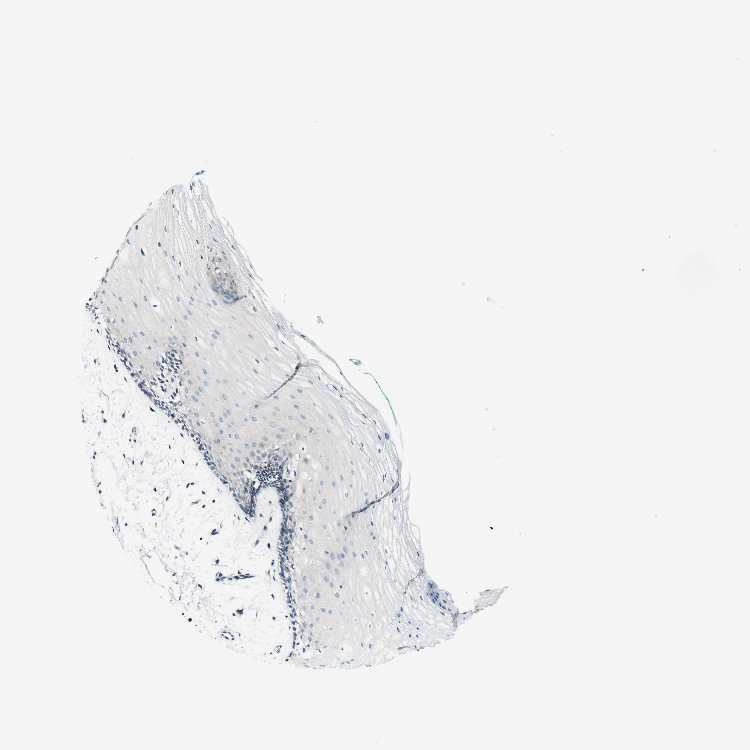

TISSUE PRIMARY DATA ORAL MUCOSA Show tissue menu

ORAL MUCOSA - Antibody stainingi

Antibody staining in the annotated cell types in the current human tissue is reported as not detected, low, medium, or high, based on conventional immunohistochemistry profiling in selected tissues. This score is based on the combination of the staining intensity and fraction of stained cells.

Each image is clickable and will lead to virtual microscopy that enables deeper exploration of all samples and also displays staining intensity scores, fraction scores and subcellular localization as well as patient and tissue information for each sample.

Antibody HPA016754

Squamous epithelial cells Not detected